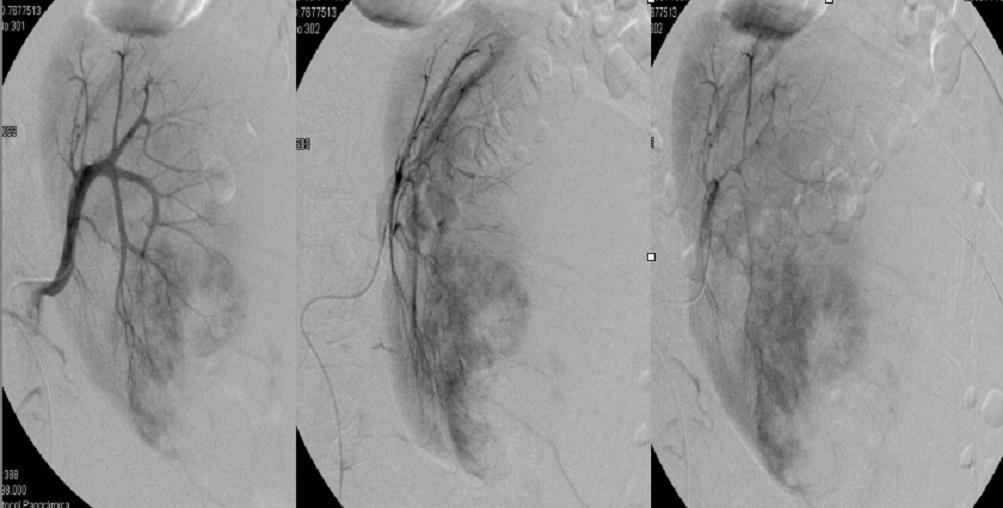

Los tumores neuroectodérmicos primitivos de origen renal (rPNET) son neoplasias excepcionales y pertenecen al grupo de tumores neuroectodérmicos periféricos malignos. Son tumores extremadamente agresivos, con tendencia a la recurrencia y a la metastatización temprana. Esta entidad pueden ser confundida con toda la variedad de tumores de células redondeadas de pequeño tamaño. De manera que es importante hacer el diagnóstico diferencial con ellas por sus implicaciones terapéuticas y pronósticas.Descargas